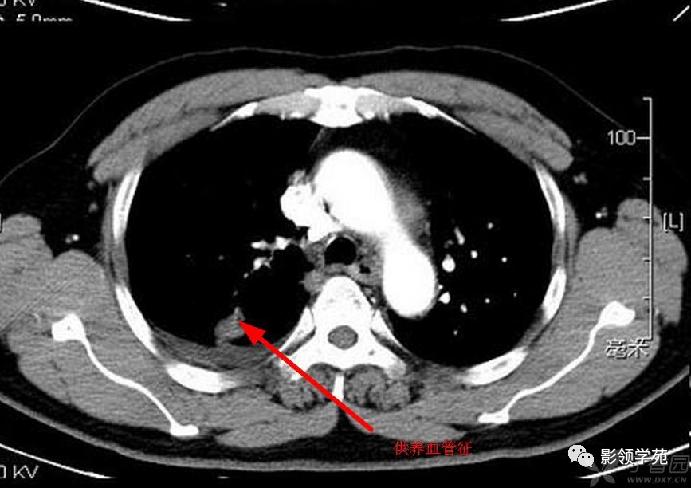

结节或肿块周围可见晕轮征、供养血管征。晕轮征提示肺结节或肿块出血,CT表现为结节或肿块周围磨玻璃密度影;供养血管征CT表现为血管影进入结节或肿块内,提示病变以血管为中心生长。

-

病例4:左肺斑片状实变,右肺中下叶结节灶,中叶结节见供养血管征。